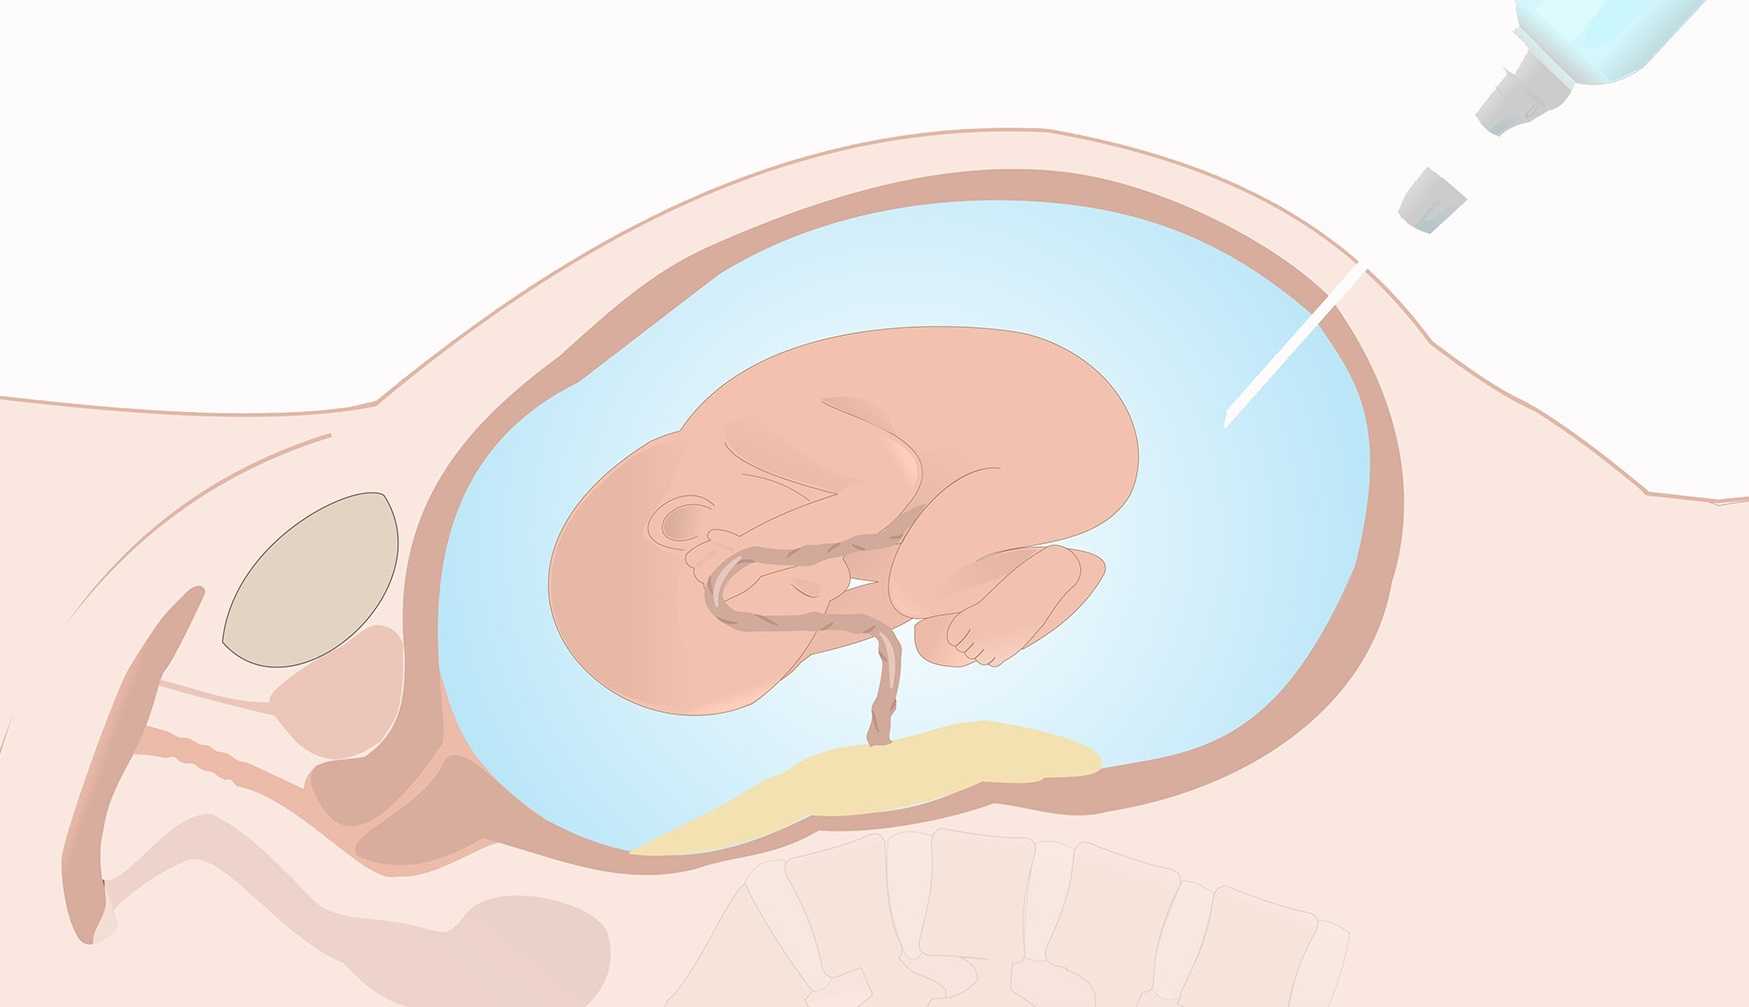

Медицинские аспекты мекония в околоплодных водах